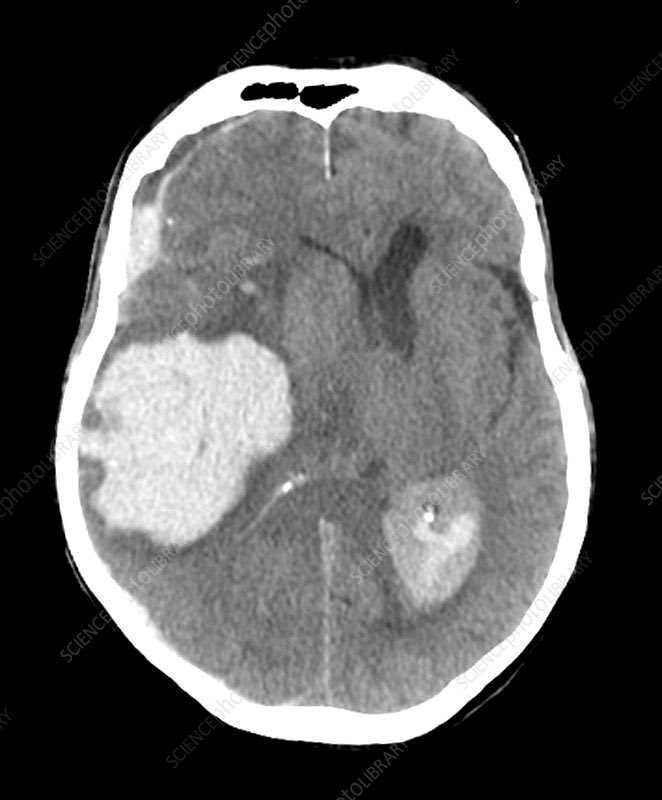

▫️intracerebral hemorrhage🩸🧠

✳️Blood in the parenchyma that is well defined